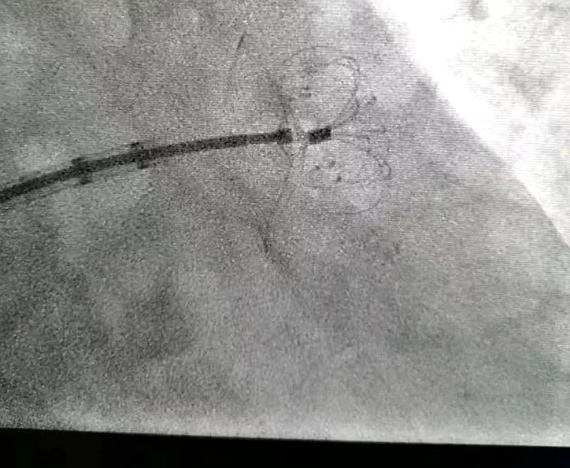

2.放造影劑

因?yàn)槊總€(gè)病人的“心耳”大小是不一樣的,為此醫(yī)生先要知道左心耳的尺寸。導(dǎo)管釋放造影劑,通過造影劑掌握左心耳的開口有多大、深度有多深,便于可以根據(jù)左心耳尺寸選擇相對應(yīng)的封堵器。

3.送封堵器

把封堵器送到左心室的尖端,導(dǎo)管脫出、封堵器張開,把這個(gè)口子堵住。

4.確認(rèn)效果

再次釋放造影劑,確認(rèn)完全封堵后結(jié)束手術(shù)。